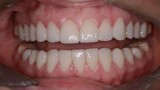

Następny etap leczenia polegał na adhezyjnym osadzeniu rekonstrukcji wykonanych z materiału E-max (Ivoclar, Liechtenstein). Po cementowaniu przystąpiono do preparacji zębów dolnego łuku zębowego. Pozostawienie wszystkich drugich zębów trzonowych w pierwotnym kształcie umożliwiło łatwą rejestrację pozycji żuchwy w RC przed rozpoczęciem preparacji, którą wykonano na twardym materiale (LuxaBite, DMG, Niemcy) (ryc. 32, 33). Po zakończeniu preparacji rejestrat zwarciowy powiększono o odcinek przedni, wykonano wyciski oraz zabezpieczono filary wcześniej przygotowanymi i podścielonymi uzupełnieniami z PMMA (ryc. 34-36). Podobnie jak w łuku górnym, w następnym etapie sprawdzono wewnątrzustnie prototyp rekonstrukcji wyfrezowany w PMMA, na którym wykonano niezbędne korekty zwarcia (ryc. 37, 38). Ostatni etap leczenia polegał na adhezyjnym cementowaniu rekonstrukcji dolnego łuku zębowego.

Ryciny 39-50 przedstawiają stan po zakończeniu leczenia.